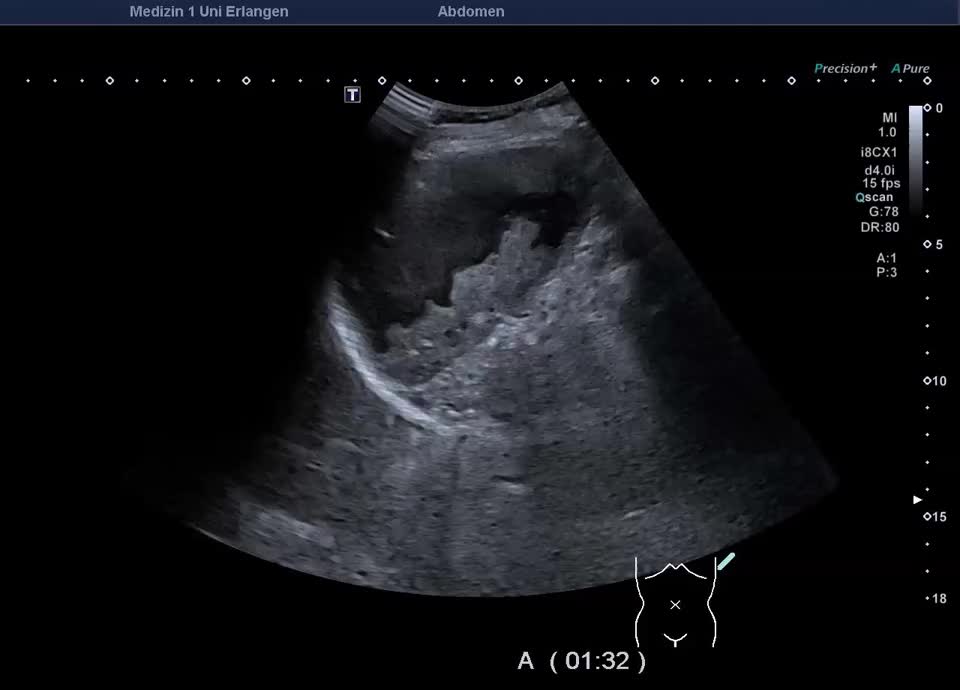

Kasuistik: 57-jährige Patientin mit einer Granulomatose mit Polyangiitis mit unklarer Leberwerterhöhung (ohne abdominelle Symptomatik). Im Ultraschall zeigt sich ein überraschender Milzbefund: Die Milz stellt sich großteils liquide dar, mit nur einem geringen Anteil soliden Gewebes, die Milzkapsel ist intakt. Die Kontrastmittelsonographie zeigt wenig erhaltenes und kontrastiertes Milzparenchym, ohne KM-Austritt in die flüssigen Anteile. Ein Trauma ist auf explizite Nachfrage nicht erinnerlich. Der Befund entspricht dem seltenen Fall einer asymptomatischen subtotalen Milznekrose, am ehesten im Rahmen einer nekrotisierenden Vaskulitis.